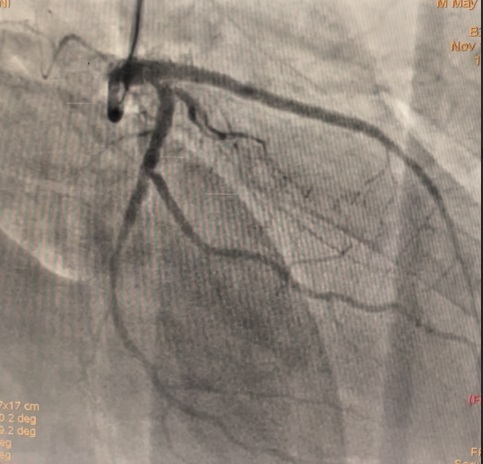

The LM had 50% ostial stenosis. LAD showed proximal CTO with bridging collaterals from the right coronary artery. LCx demonstrated proximal CTO with contralateral collaterals from the RCA. The right coronary artery was dominant with mild disease. The case represented complex dual CTO with LM involvement, posing both technical and procedural challenges due to tortuosity and calcification.

A dual access strategy was used: right radial for RCA and right femoral for LCA. For LCx CTO PCI, a Finecross microcatheter (Terumo, Japan) was advanced to the distal LCx. Predilation was done using a 2.5 ¡¿ 15 mm Firefighter balloon (Medtronic, USA) at 8 atm, followed by stenting with a 3.5 ¡¿ 30 mm Orsiro Mission drug-eluting stent (Biotronik, Germany) at 16 atm. Postdilation was performed with a 3.0 ¡¿ 15 mm Accuforce non-compliant (NC) balloon (Terumo, Japan) at 14 atm.For LAD CTO PCI, Finecross with Fielder wire (Asahi, Japan) failed to cross; Gaia First (Asahi, Japan) successfully reached the distal LAD. Predilation was performed using NC Sapphire 24 (OrbusNeich, Hong Kong) 3.5 ¡¿ 12 mm and Wedge NC (Boston Scientific, USA) 3.0 ¡¿ 15 mm. A 3.0 ¡¿ 40 mm Biofreedom Ultra stent (Biosensors, Singapore) was deployed at 14 atm. Proximal dissection into LM was noted, requiring LM–LAD stenting with 3.5 ¡¿ 22 mm Orsiro Mission and proximal optimization technique (POT) using 4.5 ¡¿ 18 mm NC Emerge balloon (Boston Scientific, USA). Intravascular ultrasound (IVUS) revealed ostial–proximal LCx disease, confirming a bifurcation lesion. Ostial LCx was predilated with a 3.5 ¡¿ 12 mm NC Sapphire balloon and stented with a 3.5 ¡¿ 14 mm Biofreedom Ultra. Final kissing balloon inflation was done with NC Sapphire 3.5 ¡¿ 12 mm (LAD) and 3.5 ¡¿ 14 mm (LCx), followed by final POT with NC Emerge 4.5 ¡¿ 8 mm balloon at 18 atm. Final shot revealed TIMI 3 flow with no dissection or perforation.

This complex case of dual CTO involving LM bifurcation was successfully treated using a dual access approach, multiple wire strategies, and IVUS-guided optimization. The procedure demonstrates that percutaneous revascularization can be a feasible alternative for surgical turn-down patients when performed with meticulous planning and imaging guidance. Optimal outcomes were achieved with POT and final kissing balloon techniques, restoring full coronary flow. This case highlights the evolving capability of complex PCI to address high-risk anatomy traditionally managed by CABG.